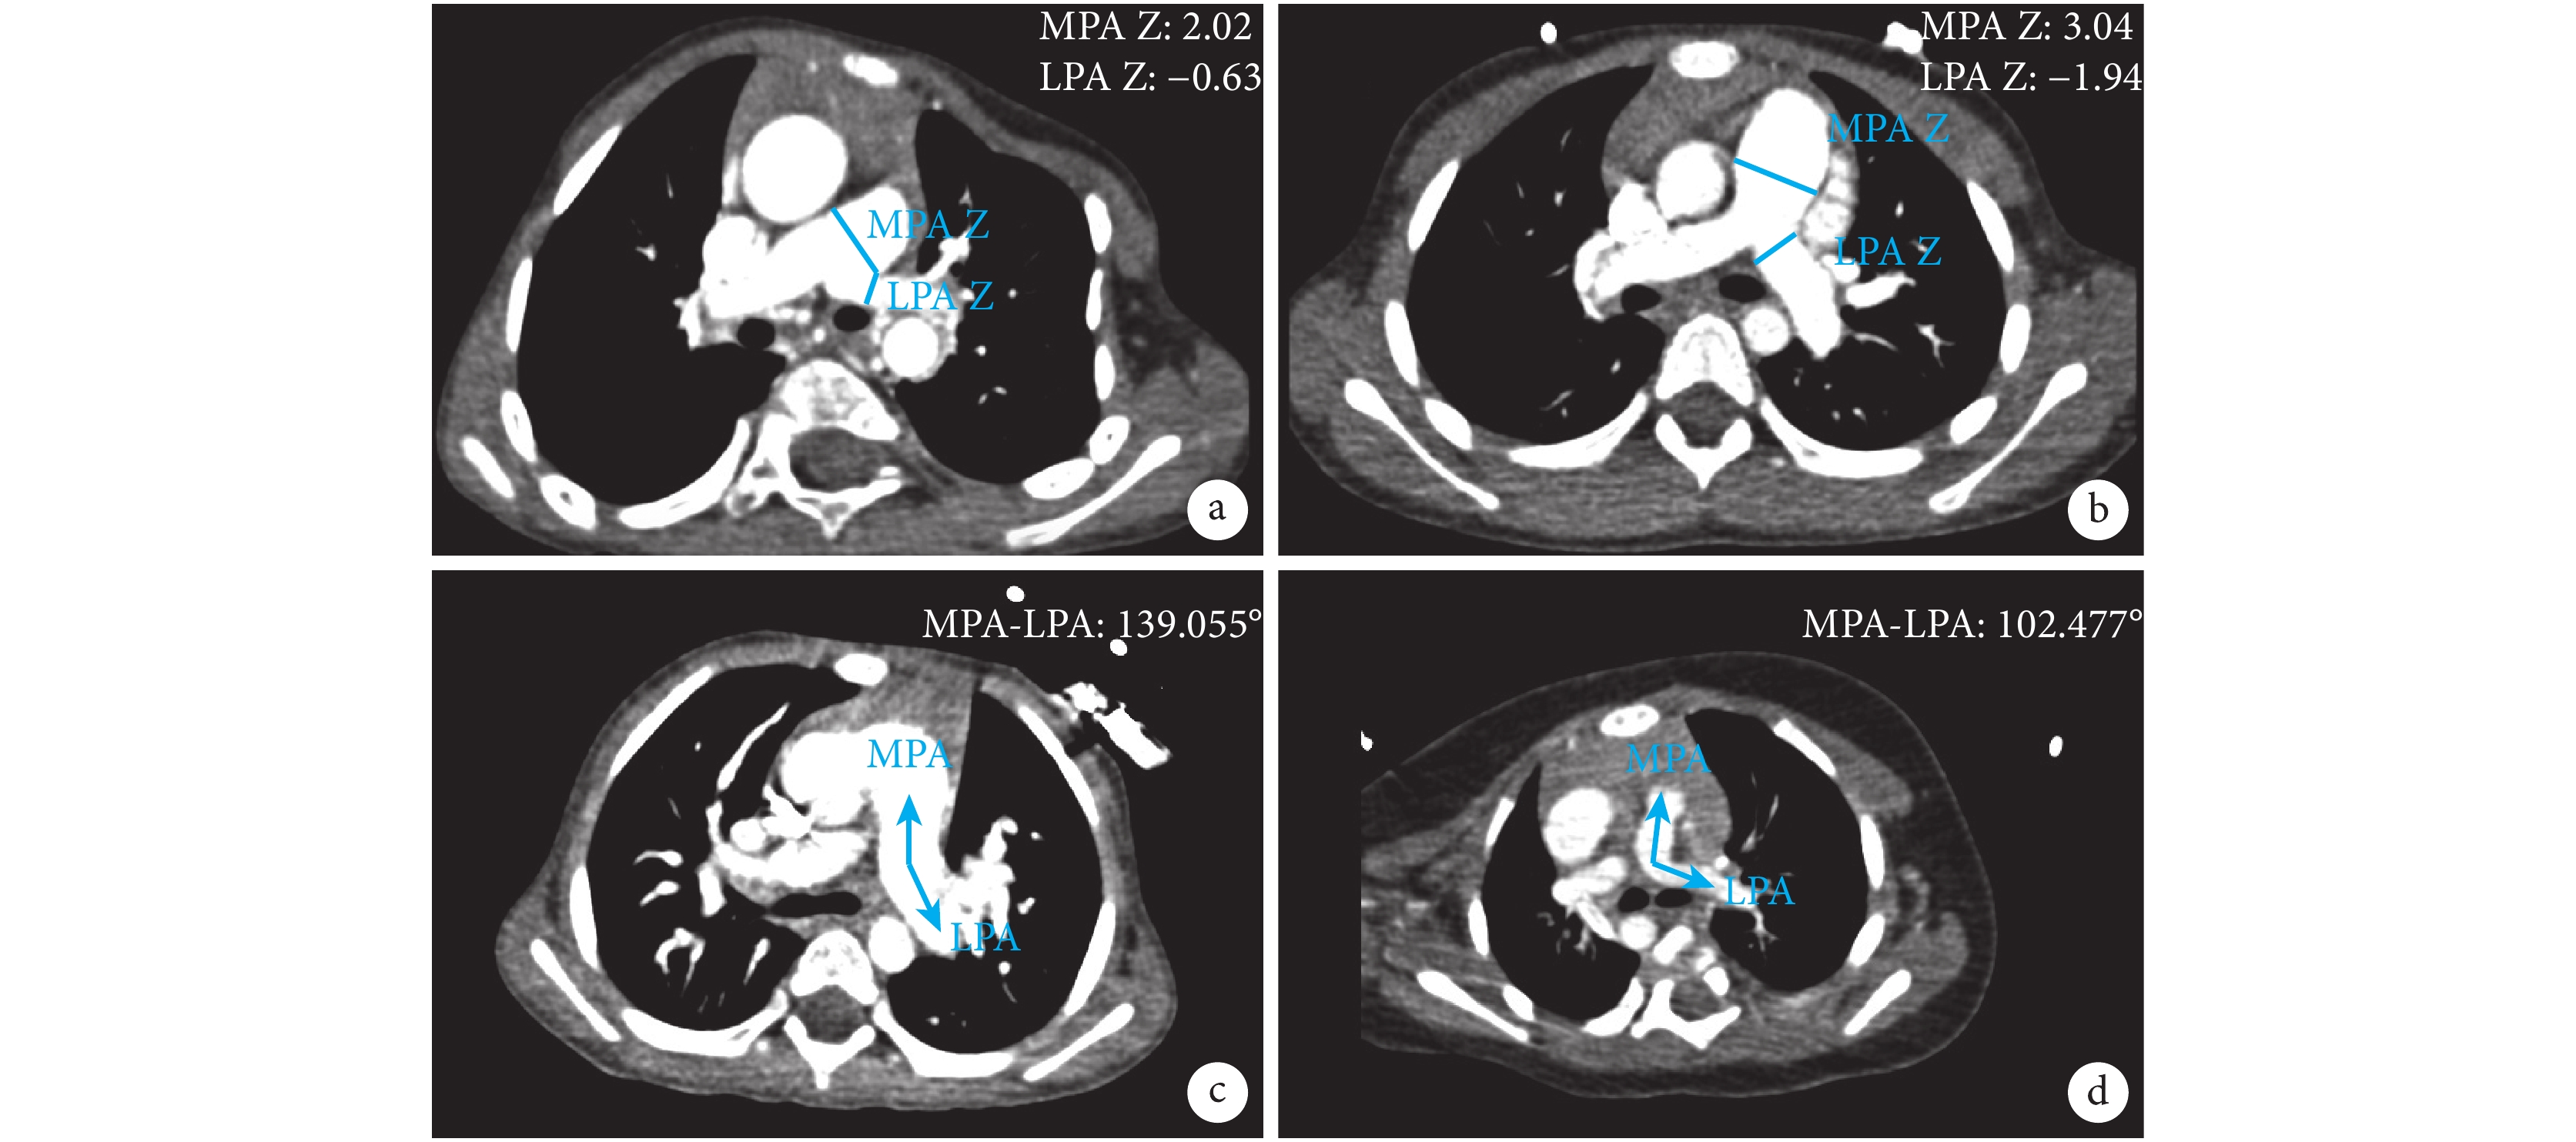

全組患者均完成 CTA 檢查。MPA 直徑在肺動脈主干處測得,LPA 直徑在主肺動脈第 1 分支節點處測得。采用 Nakata 指數和 McGoon 比值評估肺動脈發育情況,Nakata 指數為左、右肺動脈橫截面積之和與該患者體表面積的比值。McGoon 比值為左、右肺動脈在肺段動脈分支前的直徑之和與膈肌平面降主動脈直徑的比值[8-9]。LPA-MPA 夾角在 MPA 分支節點橫截面測得;見圖 1。

a:TOF 患者 MPA 與 LPA 直徑測量;b:對照組患者 MPA 與 LPA 直徑測量;c:對照組患者 MPA-LPA 夾角測量;d:TOF 患者 MPA-LPA 夾角測量;TOF:法洛四聯癥;MPA:主肺動脈;LPA:左肺動脈